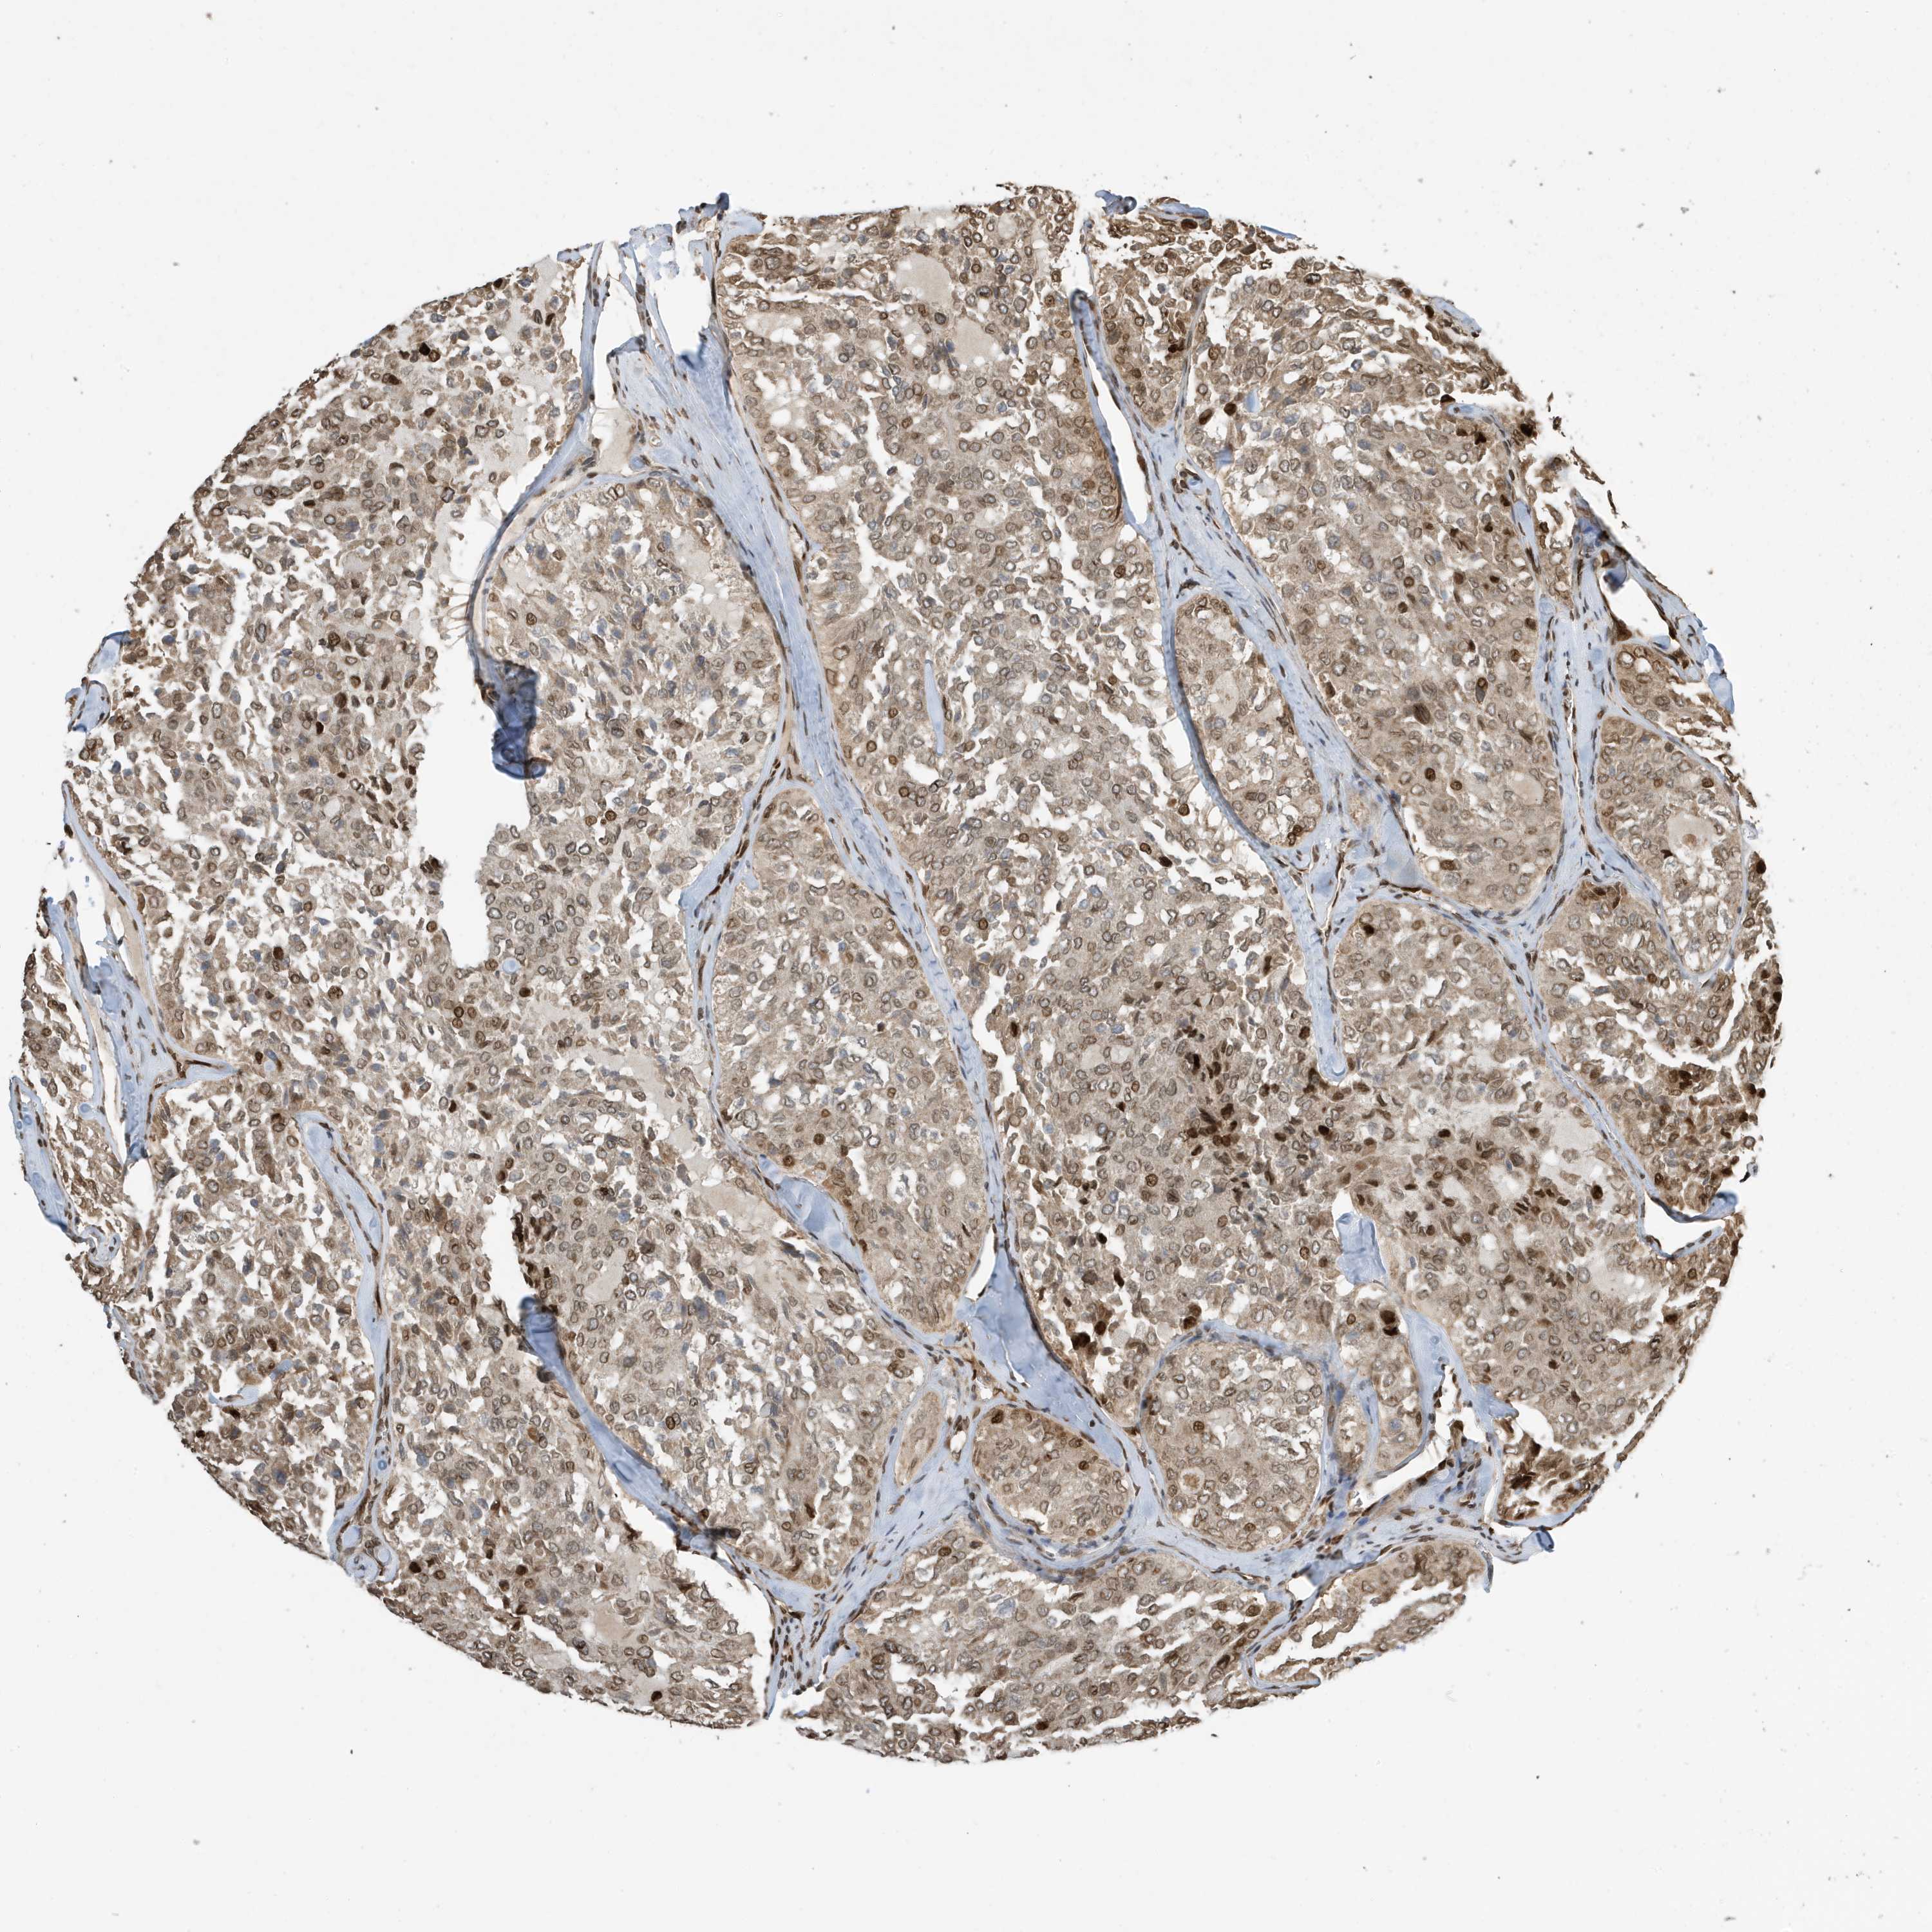

THYROID CANCER - Protein expressioni

A mouse-over function shows sample information and annotation data. Click on an image to view it in a full screen mode. Samples can be filtered based on level of antibody staining by selecting one or several of the following categories: high, medium, low and not detected. The assay and annotation is described here.

Note that samples used for immunohistochemistry by the Human Protein Atlas do not correspond to samples in the TCGA dataset.

Antibody stainingi

Antibody staining in the annotated cell types in the current human tissue is reported as not detected, low, medium, or high, based on conventional immunohistochemistry profiling in selected tissues. This score is based on the combination of the staining intensity and fraction of stained cells.

Each image is clickable and will lead to virtual microscopy that enables deeper exploration of all samples and also displays staining intensity scores, fraction scores and subcellular localization as well as patient and tissue information for each sample.

Antibody CAB034070

Staining

High

Medium

Low

Not detected

Intensity

Strong

Moderate

Weak

Negative

Quantity

>75%

75%-25%

<25%

None

Location

Nuclear

Cytoplasmic/membranous

Cytoplasmic/membranous,nuclear

Papillary adenocarcinoma, NOS

Follicular adenoma carcinoma, NOS